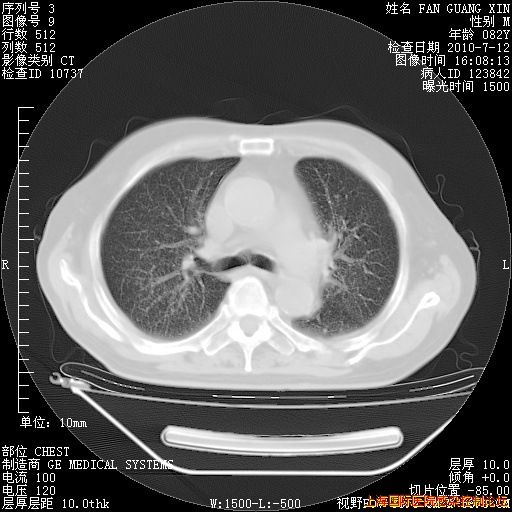

补发6月12日肺部CT肺窗

6月12日肺窗

今天复查CT

今天CT

整整相隔30天的肺部CT好像有所好转啊。甲强龙减量第3天,需要观察体温。